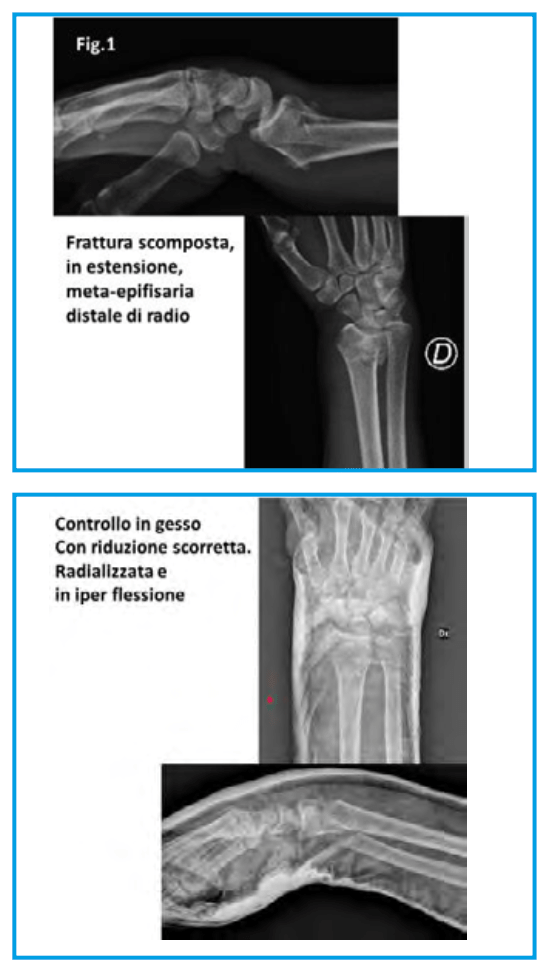

Donna di anni 58, professionista, frattura del polso destro tipo Frikman I (in iper-estensione, secondo Goyrand) sull’arto dominante. Trattamento con gesso braccio-avambraccio- mano per 35 giorni. (Fig.1)

Alla rimozione del gesso, come prima impressione (negativa), vi fu il riscontro di grave deviazione del polso in senso mediale (radializzazione), di estrema rigidità dell’articolazione e di dolore costante, determinato dal processo di guarigione, ma anche dalla grave deviazione nel verso errato, non fisiologico.

La radializzazione della frattura determinava un inpingement della stiloide del radio sulla prima filiera del carpo. Il permanere di questa situazione, oltre che dolorosa per la paziente, è anche pericolosa, perché candida la sua articolazione ad una evoluzione artrosica precoce.